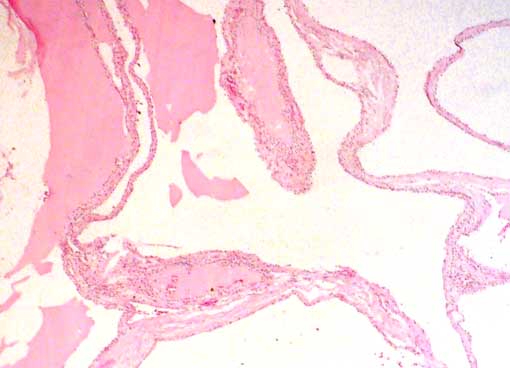

Figura 1.

H&E, X100.

No se encontraron áreas sólidas

con células claras ni había parénquima renal en los

septos.